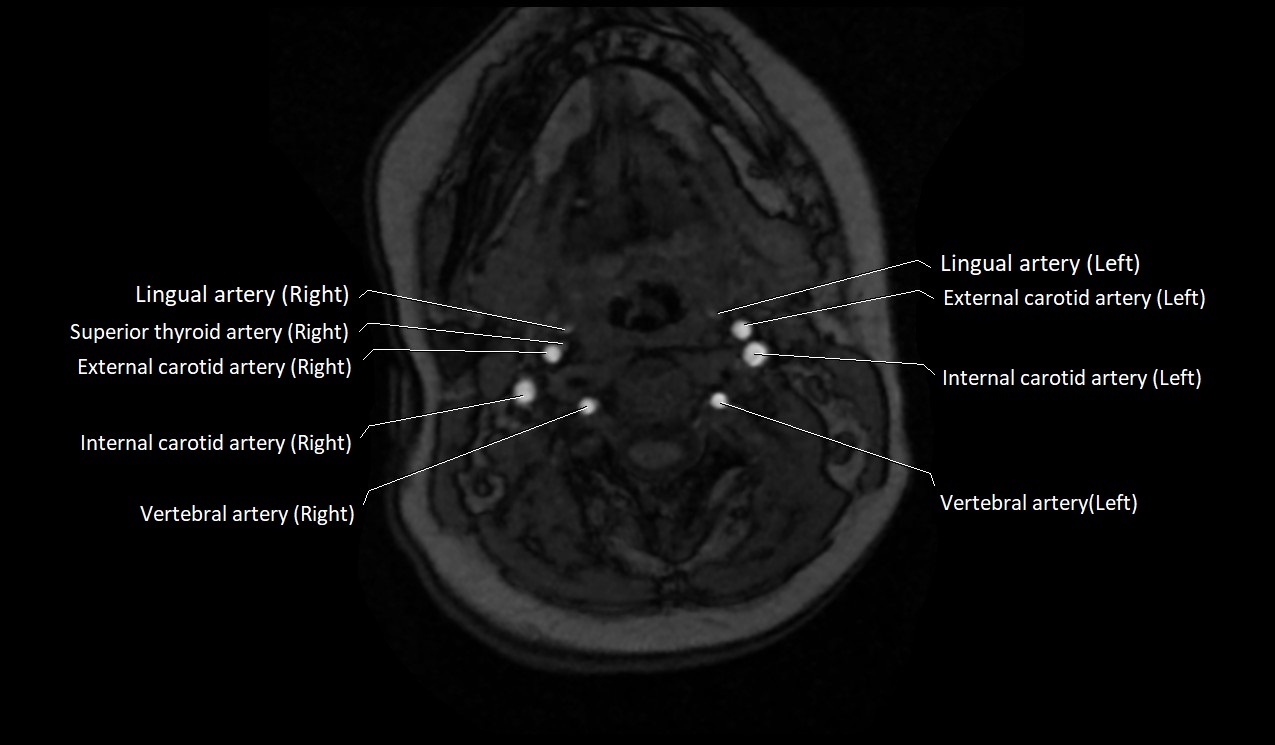

MRI images

image